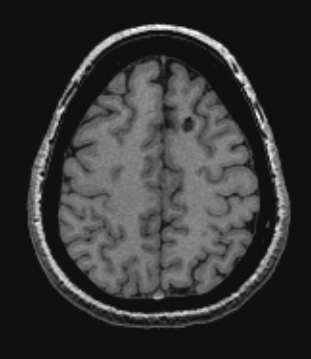

30A2,3 The lesion shown in T1-weighted scan without (30A2) and with contrast (30A3) fails to enhance.